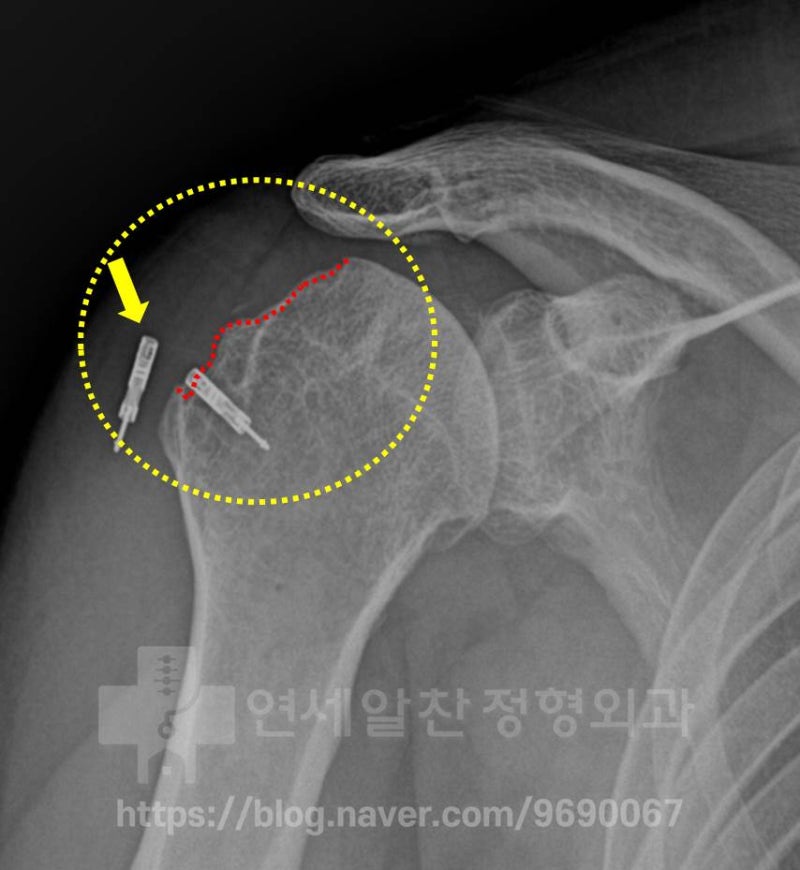

노란색 점선으로 표시된 부위를 보면 상완골의 대결절 부위가 정상적이지 않고 뭔가 손상된 것 처럼 보입니다.

빨간 점선으로 표시된 상완골의 대결절 부위 뼈의 결손이 더 심하게 진행되어 있습니다. 또한 이전 수술 당시 사용되었던 봉합나사못(노란색 화살표)이 뼈에서 빠져있는 것이 관찰됩니다.